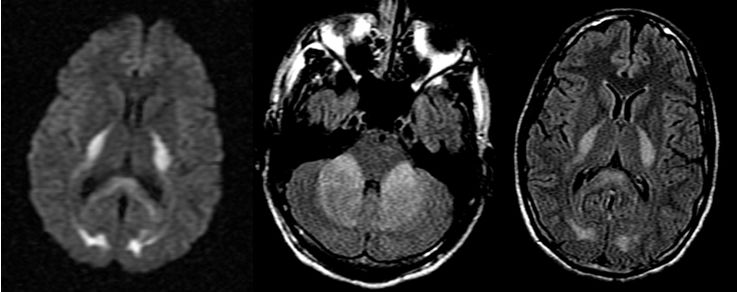

病例12

女性,75岁,发作性抽搐半月,意识障碍2天。

答案:抗GABABR抗体相关脑炎。抗GABABR抗体相关脑炎在临床上符合边缘性脑炎的表现,通常以癫痫发作、记忆力减退和意识障碍为主要特征。表现形式多样的癫痫发作是早期最突出的特征,多为继发性全身发作,还可以表现为复杂部分性发作、全面发作、全面强直-阵挛性发作、部分性运动性发作,甚至出现癫痫持续状态。患者多合并有记忆力减退和意识障碍,病程后期甚至出现幻觉和人格改变。癫痫发作也可以作为其唯一的表现。约有50%的GABABR抗体阳性患者合并小细胞肺癌,少数可合并其他肺部神经内分泌肿瘤、黑色素瘤及良性胸腺瘤等肿瘤。头MRI一侧或两侧内侧颞叶FLAIR/T2像信号增高提示该诊断的可能,但是这也见于其他自身免疫性脑炎。